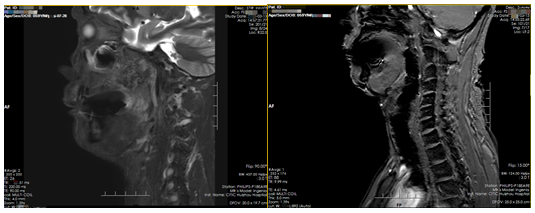

MRI影像可见:左侧颊部见不规则软组织信号影,病灶边界不清,大小约21mm×14mm×18mm,T1W1等信号,T2W1高信号,DW1稍高信号,ADC稍低信号,提示弥散受限,增强扫描呈中度不均匀强化,邻近骨质未见异常信号影,左侧颊部肿胀,T2W1稍高高信号;鼻咽、口咽大小、形态如常,其内未见明显异常信号影;包入区双侧筛实、上颌实黏膜稍增厚,双侧下鼻甲肥大。

(图:口腔MRI影像报告)

影像意见:

1.左颊部异常信号影,结合病检结果,符合恶性肿瘤

2.包入区双侧筛窦、上颌窦炎,双侧下鼻甲肥大。